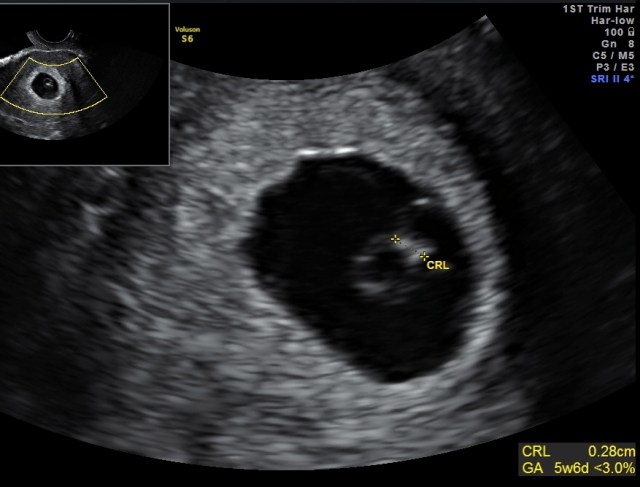

Here is a very early pregnancy at only 5 weeks of gestation. You can see that the measurement of the fetus, called CRL or crown rump length is only 2.8 millimeters! Even though the fetus is very small we were able to see the movement of the fetal heartbeat during the exam. When the fetal heartbeat is present, it means that the chance of having a miscarriage is very low.